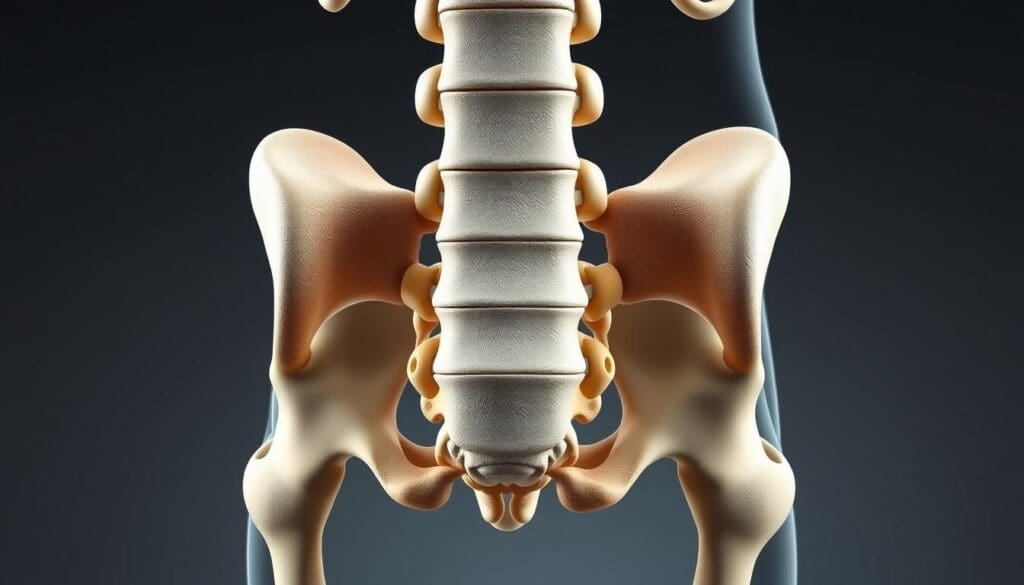

To understand a compressed spine, we must look at the spinal column’s anatomy. The spine has vertebrae, discs, and the spinal cord. These parts work together to support the body and help it move.

Structure of the Lumbar Region

The lower back, or lumbar region, has five vertebrae (L1-L5). These vertebrae carry a lot of the body’s weight. The intervertebral discs in this area help absorb shock, but they don’t have blood to heal quickly.

Vulnerable Areas for Compression

Compression can happen in the lumbar region at different spots. This includes the discs and the spinal canal. The spinal canal, where the spinal cord is, can narrow. This can press on the spinal cord or nerves.

Difference Between Disc Compression and Cord Compression

Disc compression happens when the discs between vertebrae get squished. This can cause problems like herniated discs. Cord compression, on the other hand, presses on the spinal cord. This can lead to serious neurological symptoms. Knowing the difference is key for the right treatment.